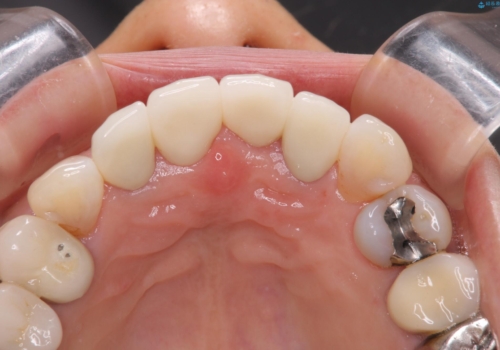

両側の前歯もやり替えをすることで、前歯の前突感も無くしています。

両側の歯の神経の治療および土台のやり替えは行っていません。